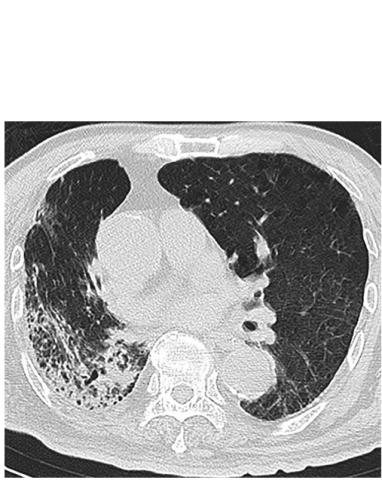

Ces chercheurs de l'hôpital de Beijing montrent que l'échographie pulmonaire est très sensible pour détecter les anomalies chez les patients COVID-19, avec en particulier une ligne pleurale épaissie et une consolidation pulmonaire fréquemment observées dans les cas plus critiques. De plus, les chercheurs suggèrent que l’imagerie pulmonaire peut également refléter la durée de l'infection.

Les 28 patients de l’étude, 14 hommes et 14 femmes, âgés de 21 à 92 ans ont obtenu des résultats positifs à la fois à l'échographie pulmonaire et au scanner thoracique. A l’échographie,

- des lignes B sont présentes chez 100% des patients,

- une consolidation pulmonaire chez 68% des patients,

- un épaissement de la ligne pleurale chez 61% des patients,

- un seul patient a présenté un petit épanchement pleural.

- L’épaississement de la ligne pleurale est plus fréquemment observé chez les patients longtemps après l'apparition initiale des symptômes, c’est-à-dire chez des patients dont la maladie dure longtemps ;

- les consolidations pulmonaires ou zones hypoéchogènes "ressemblant à des tissus", reflétant un débit d'air très réduit et une quantité accrue d'exsudat cellulaire inflammatoire sont plus fréquemment rencontrées dans les cas graves et critiques ;